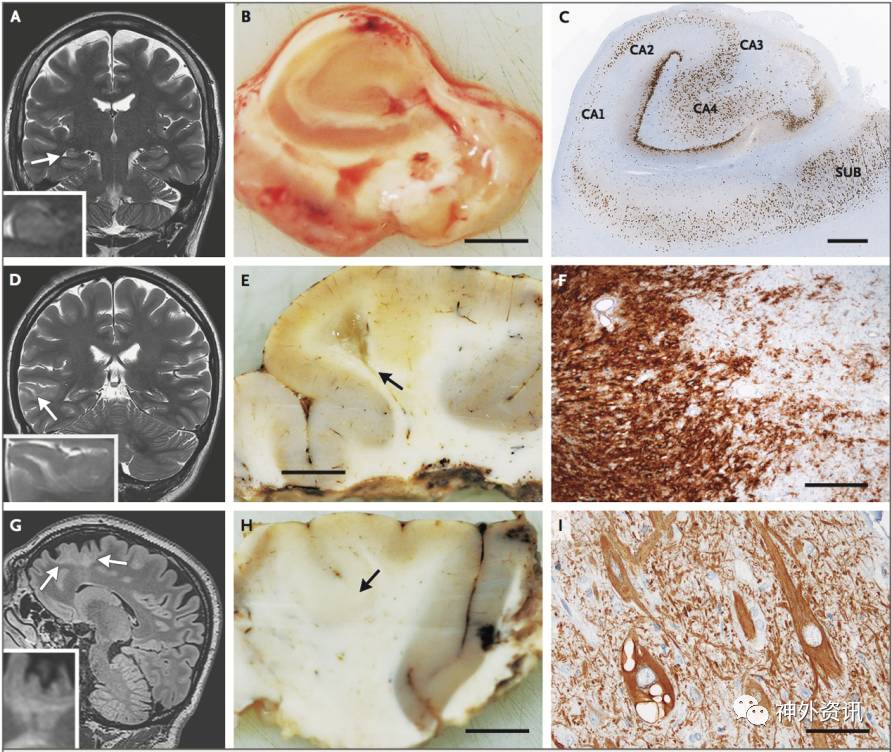

结果发现,75.9%患者癫痫发作时的年龄小于18岁,72.5%患者成年时接受手术治疗。从癫痫发作到手术切除病灶的时间间隔,成人约20.1年,儿童5.3年。71.9%的切除病灶位于颞叶,于左侧大脑半球者占49.1%,右侧占50.5%。病灶的病理学诊断主要归纳为七种类型。最常见为海马硬化,见于36.4%的癫痫患者,成年患者中海马硬化占88.7%。海马硬化患者从癫痫发病至手术平均间隔22.5年,可能与常规MRI检查难以发现海马硬化有关。颞叶的海马硬化占54.4%。而左侧颞叶海马硬化者癫痫发病年龄要早于右侧患者(10.7±9.8岁比11.9±10.2岁,P<0.001)。术后1年癫痫症状缓解率可达61.4%。第二常见为肿瘤,占23.6%,其中最多见的肿瘤类型是神经节胶质瘤(ganglioglioma),约10.4%;82.5%的神经节胶质瘤发生于颞叶;其次是胚胎发育不良性神经上皮瘤,术后1年癫痫症状缓解率68.4%;该组EEBB资料中与癫痫相关的肿瘤绝大多数是低级别肿瘤(WHO-Ⅰ级);浸润性胶质瘤罕见,可能是浸润性胶质瘤患者不在癫痫治疗中心治疗的缘故。第三常见为皮质发育畸形,占19.8%,其中局灶性皮质发育不良占皮质发育畸形的70.6%;局灶性皮质发育不良Ⅱ型的病理学成分是异形神经元和球囊细胞(表1、图1)。此外,7.7%癫痫患者病理学诊断不明确。

图1. EEBB的三种最常见癫痫灶病理学类型患者的MRI、大体标本及免疫组化结果。A.海马硬化患者MRI-T2W像,可见右侧海马萎缩(箭头所指);B.海马硬化患者的病理标本;C.海马硬化患者NeuN染色示神经元丢失;D.神经节胶质瘤患者MRI-T2W像,箭头所指为颞上回病灶;E.神经节胶质瘤患者的病理标本,箭头所指示皮质下部分囊性变;F.神经节胶质瘤的CD34染色,示肿瘤细胞浸润至临近皮质;G.局灶性皮质发育不良的MRI-FLAIR成像,箭头所指为局部皮质发育不良;H.皮质发育不良患者的病理标本;I.局部皮质发育不良的神经纤维蛋白染色见大量神经纤维聚集。